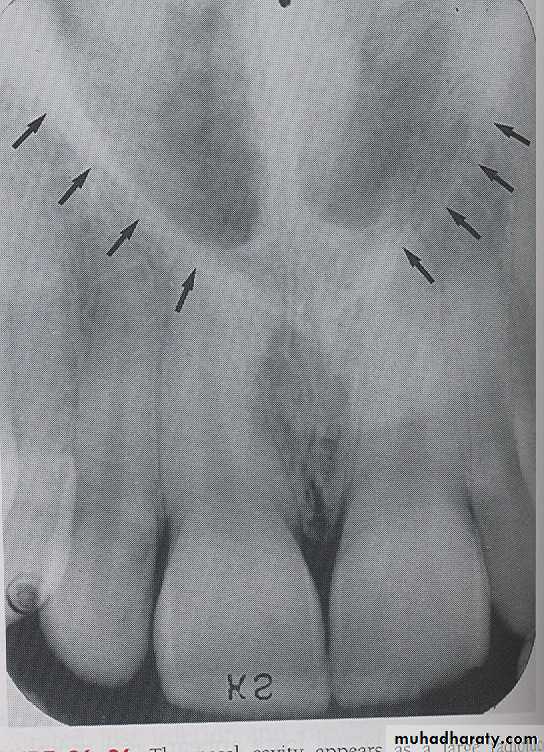

NASAL CAVITY: Is a pear-shaped compartment of bone located superior to the maxilla. On a maxillary perapical radiograph the nasal cavity appears as a large radiolucent area above the maxillary incisor.

NASAL SEPTUM:

The nasal septum is a vertical bony wall that divides the nasal cavity into right and left nasal fosse. Radiographically nasal septum appears as a vertical radiopaque partition that divide the nasal cavity.

ANTERIOR NASAL SPINE

: Is a sharp projection of the maxilla located at the anterior portion of nasal cavity. Radiographically the anterior nasal spin appears as a V shaped radiopaque area located at the intersection of the floor of nasal cavity and the nasal septum.

Inferior Nasal Conchae

Inferior nasal conchae are plates of bone that extend from the lateral walls of the nasal cavity. Inferior nasal conchae are seen in the lower lateral portions of the nasal cavity.Radiographically, inferior nasal conchae appear as a diffuse radiopaque mass or projection within the nasal cavity